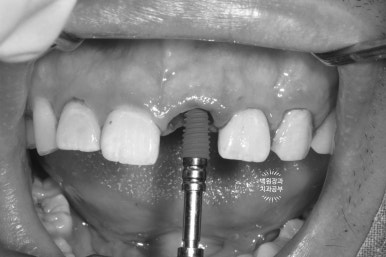

이를 뽑은 자리에 조심스럽게 오스템 BA 임플란트 고정체 (fixture)을 위치시킵니다.

최종 보철물을 만드는데 있어, 주변치아와의 관계를 고려한 임플란트의 위치와 깊이가 가장 중요하기에 많은 경험을 바탕으로 신중하게 해내야해요!!

잘 위치된 임플란트 고정체 (fixture)에 임시 지대주를 연결해줍니다.

임시 지대주의 크기는 정해져 있기 때문에, 구강 내 상황은 환자마다 다르므로 그 형태를 다듬어 주어야 합니다.

비유하자면... 키가 작은 사람은 똑같은 기성 청바지를 사도 바지 끝단을 잘라야 하잖아요!!???

임시 지대주의 길이를 짧게 다듬어 아래 앞니에 닿지 않는 것을 확인하고,

그 내부를 임시 재료로 메꿔준 다음에

준비해두었던 임시치아를 연결해주게 됩니다.